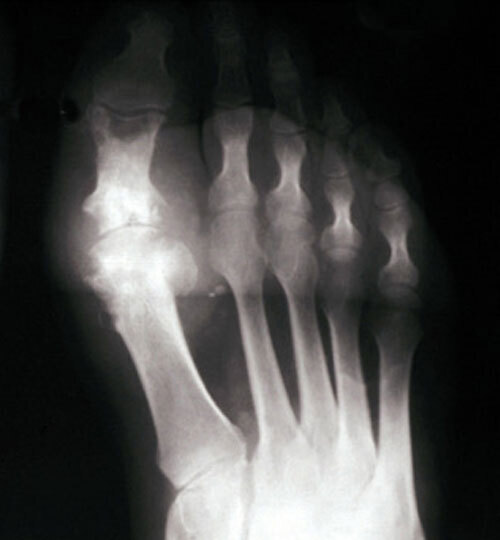

Le patient non traité par hypo-uricémiant peut développer une goutte polyarticulaire chronique caractérisée par des articulations douloureuses et gonflées en permanence, l’apparition de tophus (fig. 1) voire d’une arthropathie destructrice (fig. 2 et 3), et des manifestations rénales (lithiase rénale, le plus souvent uratique, néphropathie interstitielle …).

La forme pseudorhumatoïde est rare (5 %), simulant une polyarthrite rhumatoïde (diagnostic différentiel), avec parfois des signes systémiques d’inflammation (élévation de la vitesse de sédimentation et de la CRP). Le diagnostic repose sur la mise en évidence des cristaux de PPC. La radio peut mettre en évidence des calcifications des cartilages articulaires (fig. 6) et des fibrocartilages (fig. 7, 8, 9 et 10). L’échographie (plus sensible) peut mettre en évidence des dépôts de PPC, qui apparaissent comme une fine bande hyperéchogène au sein des cartilages hyalins et comme des points scintillants dans les fibrocartilages ou dans la membrane synoviale. Dans l’arthrite chronique à PPC, lespossibilités thérapeutiques sont, par ordre de préférence : colchicine (de 0,5 à 1 mg/j), petites doses de cortisone, parfois les AINS per os (mais leur prescription est souvent limitée par les comorbidités chez les patients âgés), méthotrexate et l’hydroxychloroquine. Il n’y a pas aujourd’hui de traitement « de fond », mais des molécules sont à l’étude.